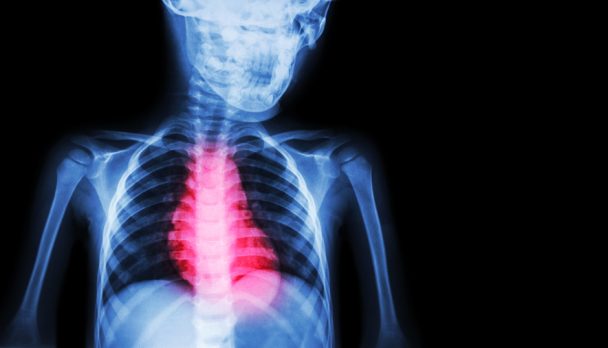

Associate Professor Stephan Foy provides a practical framework for investigation.